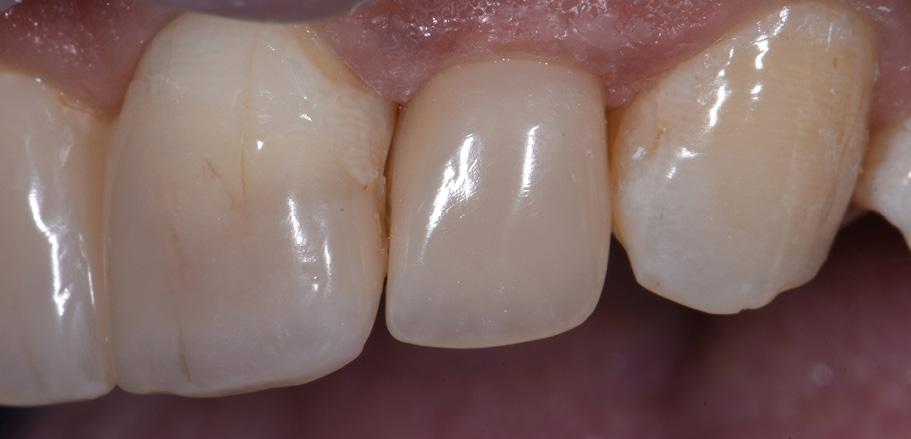

Restoring The Lateral Incisors

Tooth preparation was not required on the lateral incisors. Instead, they were merely cleaned after a slight roughening of the enamel surfaces. The build-up procedure was similar to the one used for the central incisors. The adjacent tooth was protected with PTFE tape, and the palatal shell was created with the aid of a finger instead of a silicone index. Afterwards, we focused on the build-up of the interproximal walls before a small amount of dentin was placed and the shape was finalized by applying the labial enamel layer.

Fig. 6 Situation after finalization of the central incisor restorations with composite in the enamel opacity.

Fig. 4 Light-cured palatal shells made of CLEARFIL MAJESTY™ ES-2 Premium in the shade A3E.

Fig. 7 Central incisor restorations after finishing and initial polishing.

Fig. 5 Build-up of the dentin core with mamelons individualized with the shade WD and brown stain.

Fig. 8 Build-up of the left lateral incisor.

Conclusion

Two different opacities, a single shade combination and some bleached shade plus stain for special effects – in the present patient case, a simple formula allowed us to create lifelike anterior restorations. With one enamel and one dentin paste used, it is possible to simply rebuild the natural anatomy without the risk of ending up with a bulky core that – once reduced – will lose its special optical structure. It is also easy to control the thickness of the final enamel layer with its huge impact on the light-optical properties of the whole restoration. For most patients and teeth with a simple or medium-to-complex internal colour structure, the selected concept is very well suited and will lead to pleasing outcomes.